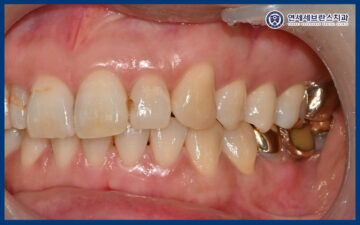

25.03.20

그리고 주변 치아와 조화를 이룰 수 있도록

색상과 형태를 세심하게 고려하여

보철물을 제작하였습니다.

이를 통해 자연치아와

크게 구분되지 않으면서

심미성과 기능을 동시에

회복할 수 있도록 하였습니다.